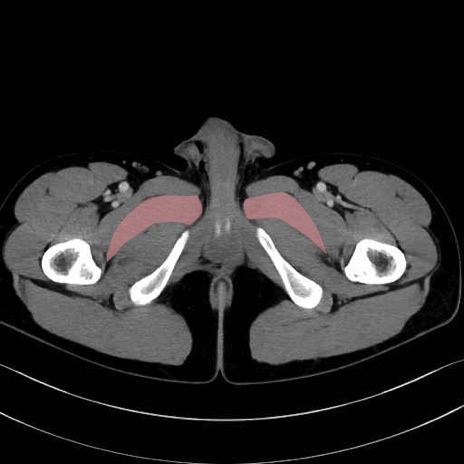

短内転筋(Adductor brevis) のCT画像の解剖

短内転筋 (Adductor brevis)